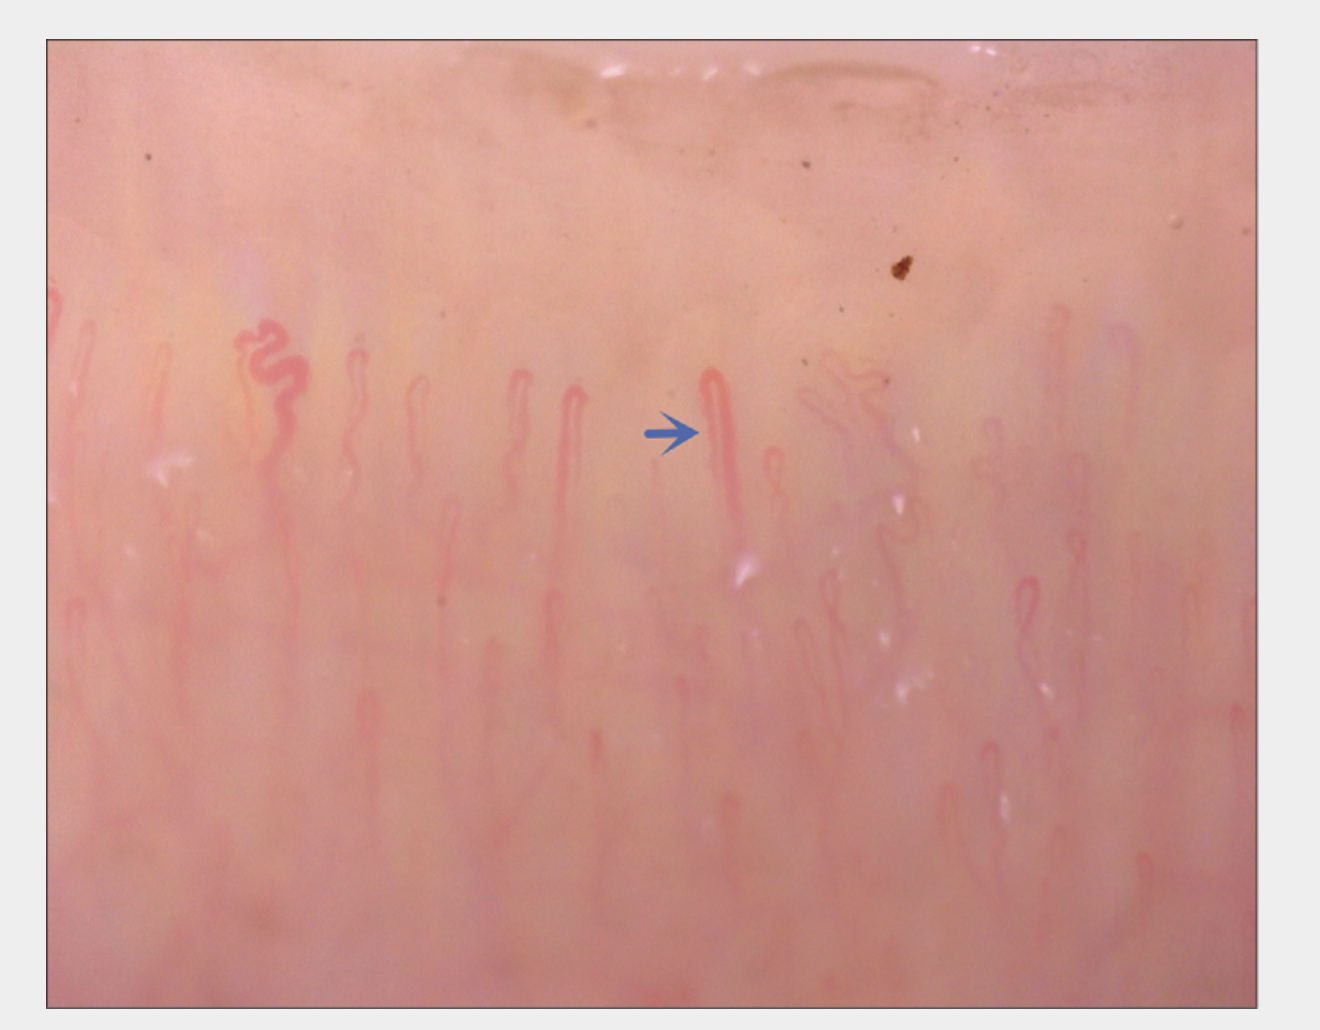

DISORGANIZED CAPILLARIES

Disorganized capillary areas are More Common in Nail Capillaries from Patients with Androgenetic Alopecia Compared to Controls. Source: Cao L et al. Nailfold capillaroscopy alterations in androgenetic alopecia: A cross-sectional study. Indian J Dermatol Venereol Leprol. 2022 Feb 28;1-7. Image shown with creative commons license.

AVASCULAR CAPILLARY AREAS

Avascular areas are More Common in Nail Capillaries from Patients with Androgenetic Alopecia Compared to Controls. Source: Cao L et al. Nailfold capillaroscopy alterations in androgenetic alopecia: A cross-sectional study. Indian J Dermatol Venereol Leprol. 2022 Feb 28;1-7. Image shown with creative commons license.